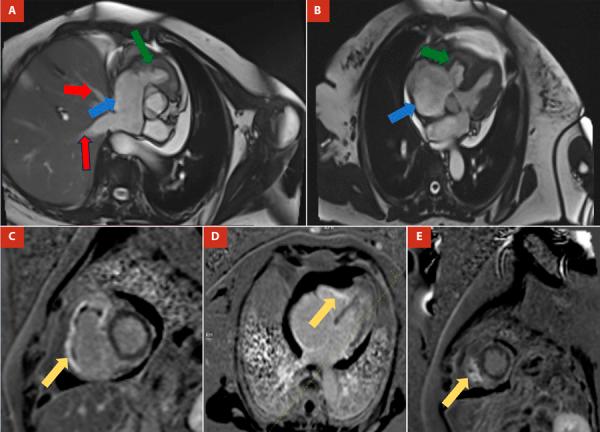

Endomyocardial fibrosis or Davies disease is a rare cause of restrictive cardiomyopathy. It is characterized by the deposit of fibrous material in the endocardium that leads to quickly progressive heart failure. It most frequently affects both ventricles, with isolated involvement of the right ventricle being the least common form. The clinical presentation of this entity is based on symptoms of right heart failure, although arrhythmias and conduction disorders may also be present. The treatment is determined by the management of congestion and surgical intervention in symptomatic patients. We present the first case of endomyocardial fibrosis isolated from the right ventricle in Colombia, we describe the clinical, etiological, imaging and management characteristics in order to deliver to the medical community an approximate understanding of this disease focusing on an unusual way of presentation.

心内膜心肌纤维化或戴维斯病是限制性心肌病的一种罕见病因。其特征是心内膜出现纤维物质沉积,导致心力衰竭快速进展。它最常累及双心室,孤立累及右心室是最不常见的形式。该疾病的临床表现基于右心衰竭症状,不过也可能出现心律失常和传导障碍。治疗取决于对充血的处理以及对有症状患者的手术干预。我们报告了哥伦比亚首例孤立性右心室心内膜心肌纤维化病例,描述了其临床、病因、影像学及治疗特点,以便让医学界对这种疾病以一种不寻常的呈现方式有大致了解。